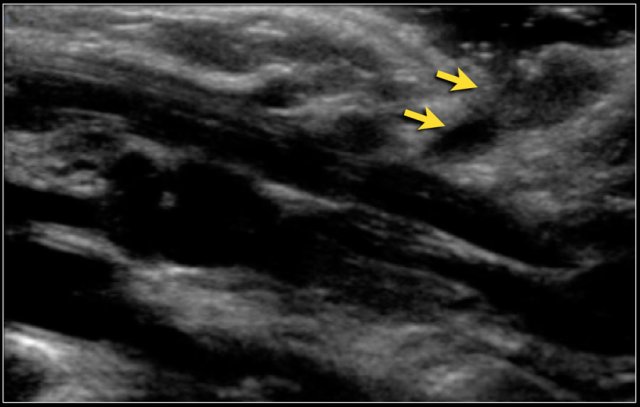

Branchial sinuses are blind ending tracts, presenting anterior of the sternocleidomastoid muscle.

Branchial second arch fistulas end in the tonsillar fossa, as can be demonstrated with a contrast fistulogram or MRI.

With ultrasound a tract can often be seen to travel upwards, but it is usually not possible to depict the proximal ending.

Here a two-year-old boy with a dirty spot in the right lower neck.

A small tract could be seen to extend inwards.

At operation a second branchial fistula was excised.

Here a ten-year-old girl with a pit in the right neck, anterior of the sternocleidomastoid muscle.

On US a long cystic lesion can be seen which can be traced up to the right submandibular region.

At operation, the fistula extended towards the right tonsillar fossa and was excised.